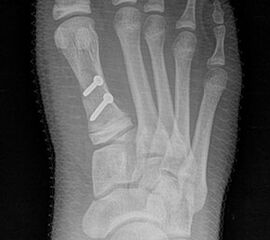

Röntgen

Standard ist die belastete Röntgenaufnahme des Fußes dorso-plantar und seitlich. Günstig ist eine Röhrenkippung von 10°-20°, um die Gelenke der Lisfranc-Linie einsehen zu können.

Ergänzend kann eine Schrägaufnahme hilfreich sein. Bei Metatarsalgien oder Pathologien der Sesambeine liefert die Sprinteraufnahme zusätzliche Informationen. Bei einer Pes planovalgus Fehlstellung wird ergänzend ein Saltzman view durchgeführt.

• Hallux valgus Winkel

• Hallux valgus interphalangeus Winkel

• Intermetatarsalwinkel I zu II

• Distaler Metatarsale Gelenkwinkel (PASA)

• Form des Mittelfußknochenkopfes

• Winkel Metatarsale I Basis zum Os cuneiforme mediale

• Metatarsalindex

• Elevation/ Plantarisierung I. Strahl

• Pes metatarsus adductus

• Wachstumsfugen

• Coalitiones

• Akzessorische Knochen